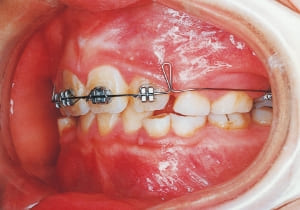

7 At start of Phase 1 Treatment 3-28-’88

8 Phase 1 Treatment progress 1-25-’89 10 months after start of treatment

The first phase of treatment involved extracting the left and right maxillary deciduous canines. The space created was used to forcibly retract the four anterior teeth, thereby aiming to improve lip closure function (6–9, 11). Morphological changes suggest that lip function differed before and after treatment (6, 9). Subsequently, the first premolars erupted, but extraction is planned to secure space for canine eruption (10). A Class II molar relationship remains, but the significant overjet has improved (11).